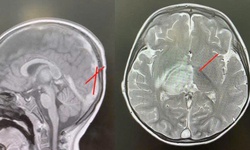

Thuốc mới trị bệnh u vàng não, tình trạng tích tụ lipid hiếm gặp

Thuốc mới - 17/03/2025 14:00SKĐS - Thuốc ctexli (chenodiol) vừa được Cục Quản lý Thực phẩm và Dược phẩm Hoa Kỳ phê duyệt để điều trị bệnh u vàng não gân ở người lớn. Đây là loại thuốc đầu tiên được FDA chấp thuận để điều trị tình trạng này, một bệnh tích trữ lipid rất hiếm gặp.